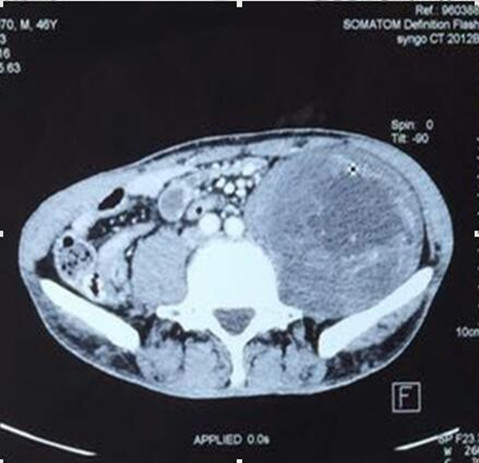

左侧盆腔椎体旁腹膜后巨大肿物切除

赵先生45岁,于2015年7月发现左侧腹部有一无痛性肿物,约鸡蛋大小,赵先生认为这肿物不痛不痒,就没重视。可随着时间推移,肿物逐渐增大,李先生出现左下肢疼痛、麻木的症状,包块增长至约拳头大小,疼痛明显加重,甚至无法入睡,严重影响李先生生活质量,仅半年时间,体重减轻10kg,在外院行增强CT检查示:“左侧腹膜后占位,考虑间叶源性肿瘤可能性大”。为求进一步诊治,李先生多方打听来我院骨外一科就诊。确诊后,白玉江主任决定为此其行肿物切除术。术中见腹外斜肌下方肿物,手术难度及风险极大,经过两个小时的手术,最终将15×10×10cm3巨大肿瘤完整切除。术后病理回报:粘液性脂肪肉瘤。术后一个月及两个月随访,患者左下肢疼痛无复发。

手术难度:由于患者有肿瘤病史,且此重物巨大在盆腔内,无活动度,手术难度极大,因肿物巨大与周围组织粘连,手术时间较长,并极有可能造成输尿管、腹膜、肠管、神经的损伤;该肿瘤恶性可能性大,若侵犯周围组织,需扩大切除;其中最危险的是肿物在盆腔与左髂骨粘连且无活动度,若将其完整切除极有可能损伤盆底静脉丛,造成大量失血,引起失血性休克导致患者死亡。

入院后腹部MRI